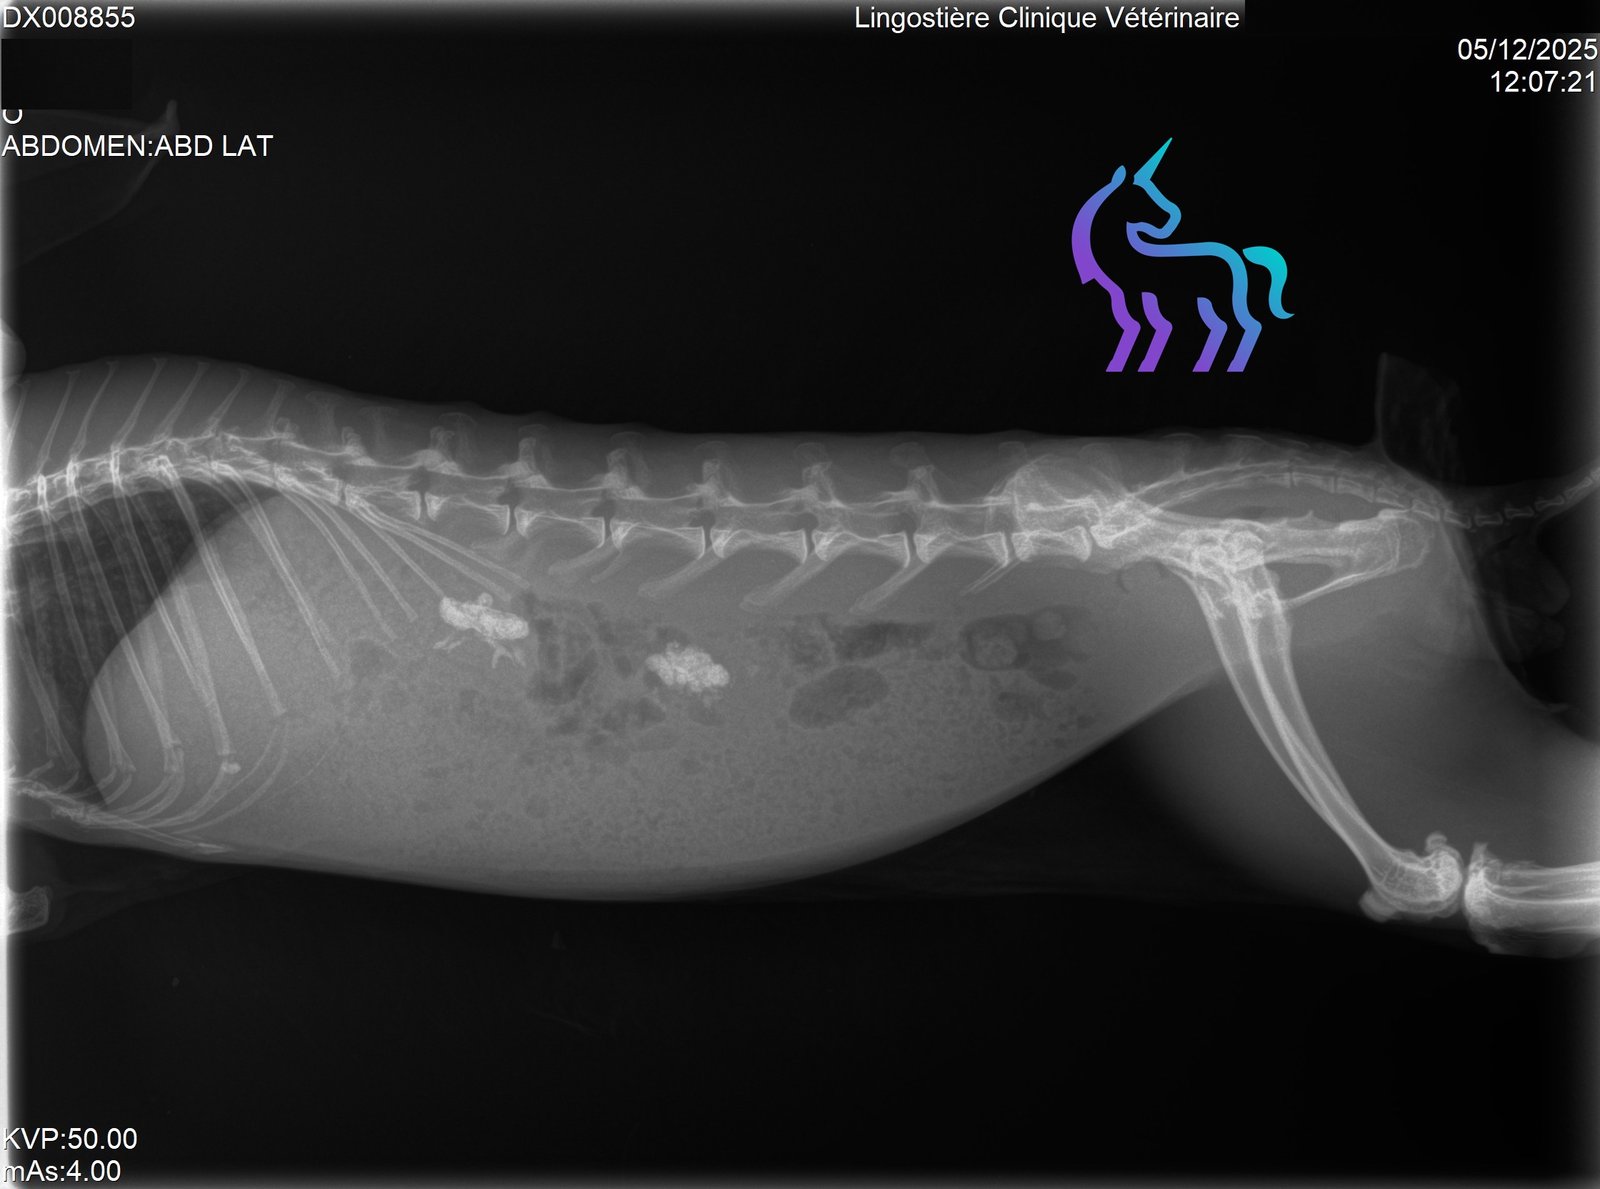

Oui (bassin, membres). Une douleur importante peut entraîner anorexie puis stase digestive.

Quels examens sont utiles ?

Radiographies pour fractures/arthrose, scanner/IRM si suspicion lésion vertébrale.Amputation : dans quels cas ?